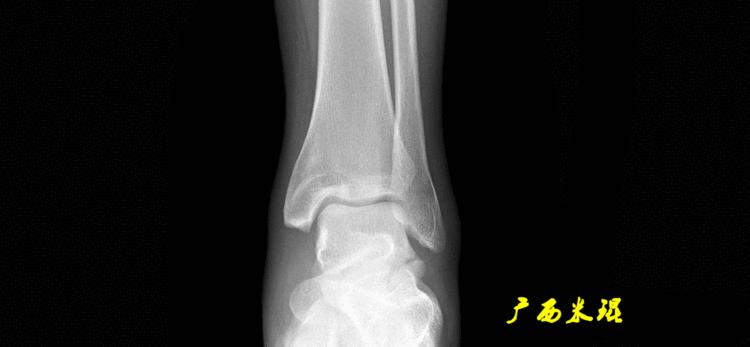

(3)踝关节中心

踝关节中心点常用的也有3个,分别是骨骼(内、外踝表面间距)中点、踝关节间隙水平软组织中点和距骨宽度中点。

胫骨远端外侧角(mLDTA):胫骨远端切线(关节线)与下肢力线(机械轴)两者之间的外侧夹角,正常为89°±3°。

解剖胫骨远端外侧角(aLDTA):胫骨远端切线(关节线)与胫骨解剖轴两者之间的外侧夹角,正常为89°±3°。由于胫骨解剖轴与机械轴几乎一致,所以一般解剖胫骨远端内侧角与机械胫骨远端内侧角一致。

胫骨远端前倾角(ADTA):矢状面上胫骨远端的关节切线与胫骨解剖轴形成的夹角叫胫骨远端前倾角,正常为80°±2°。